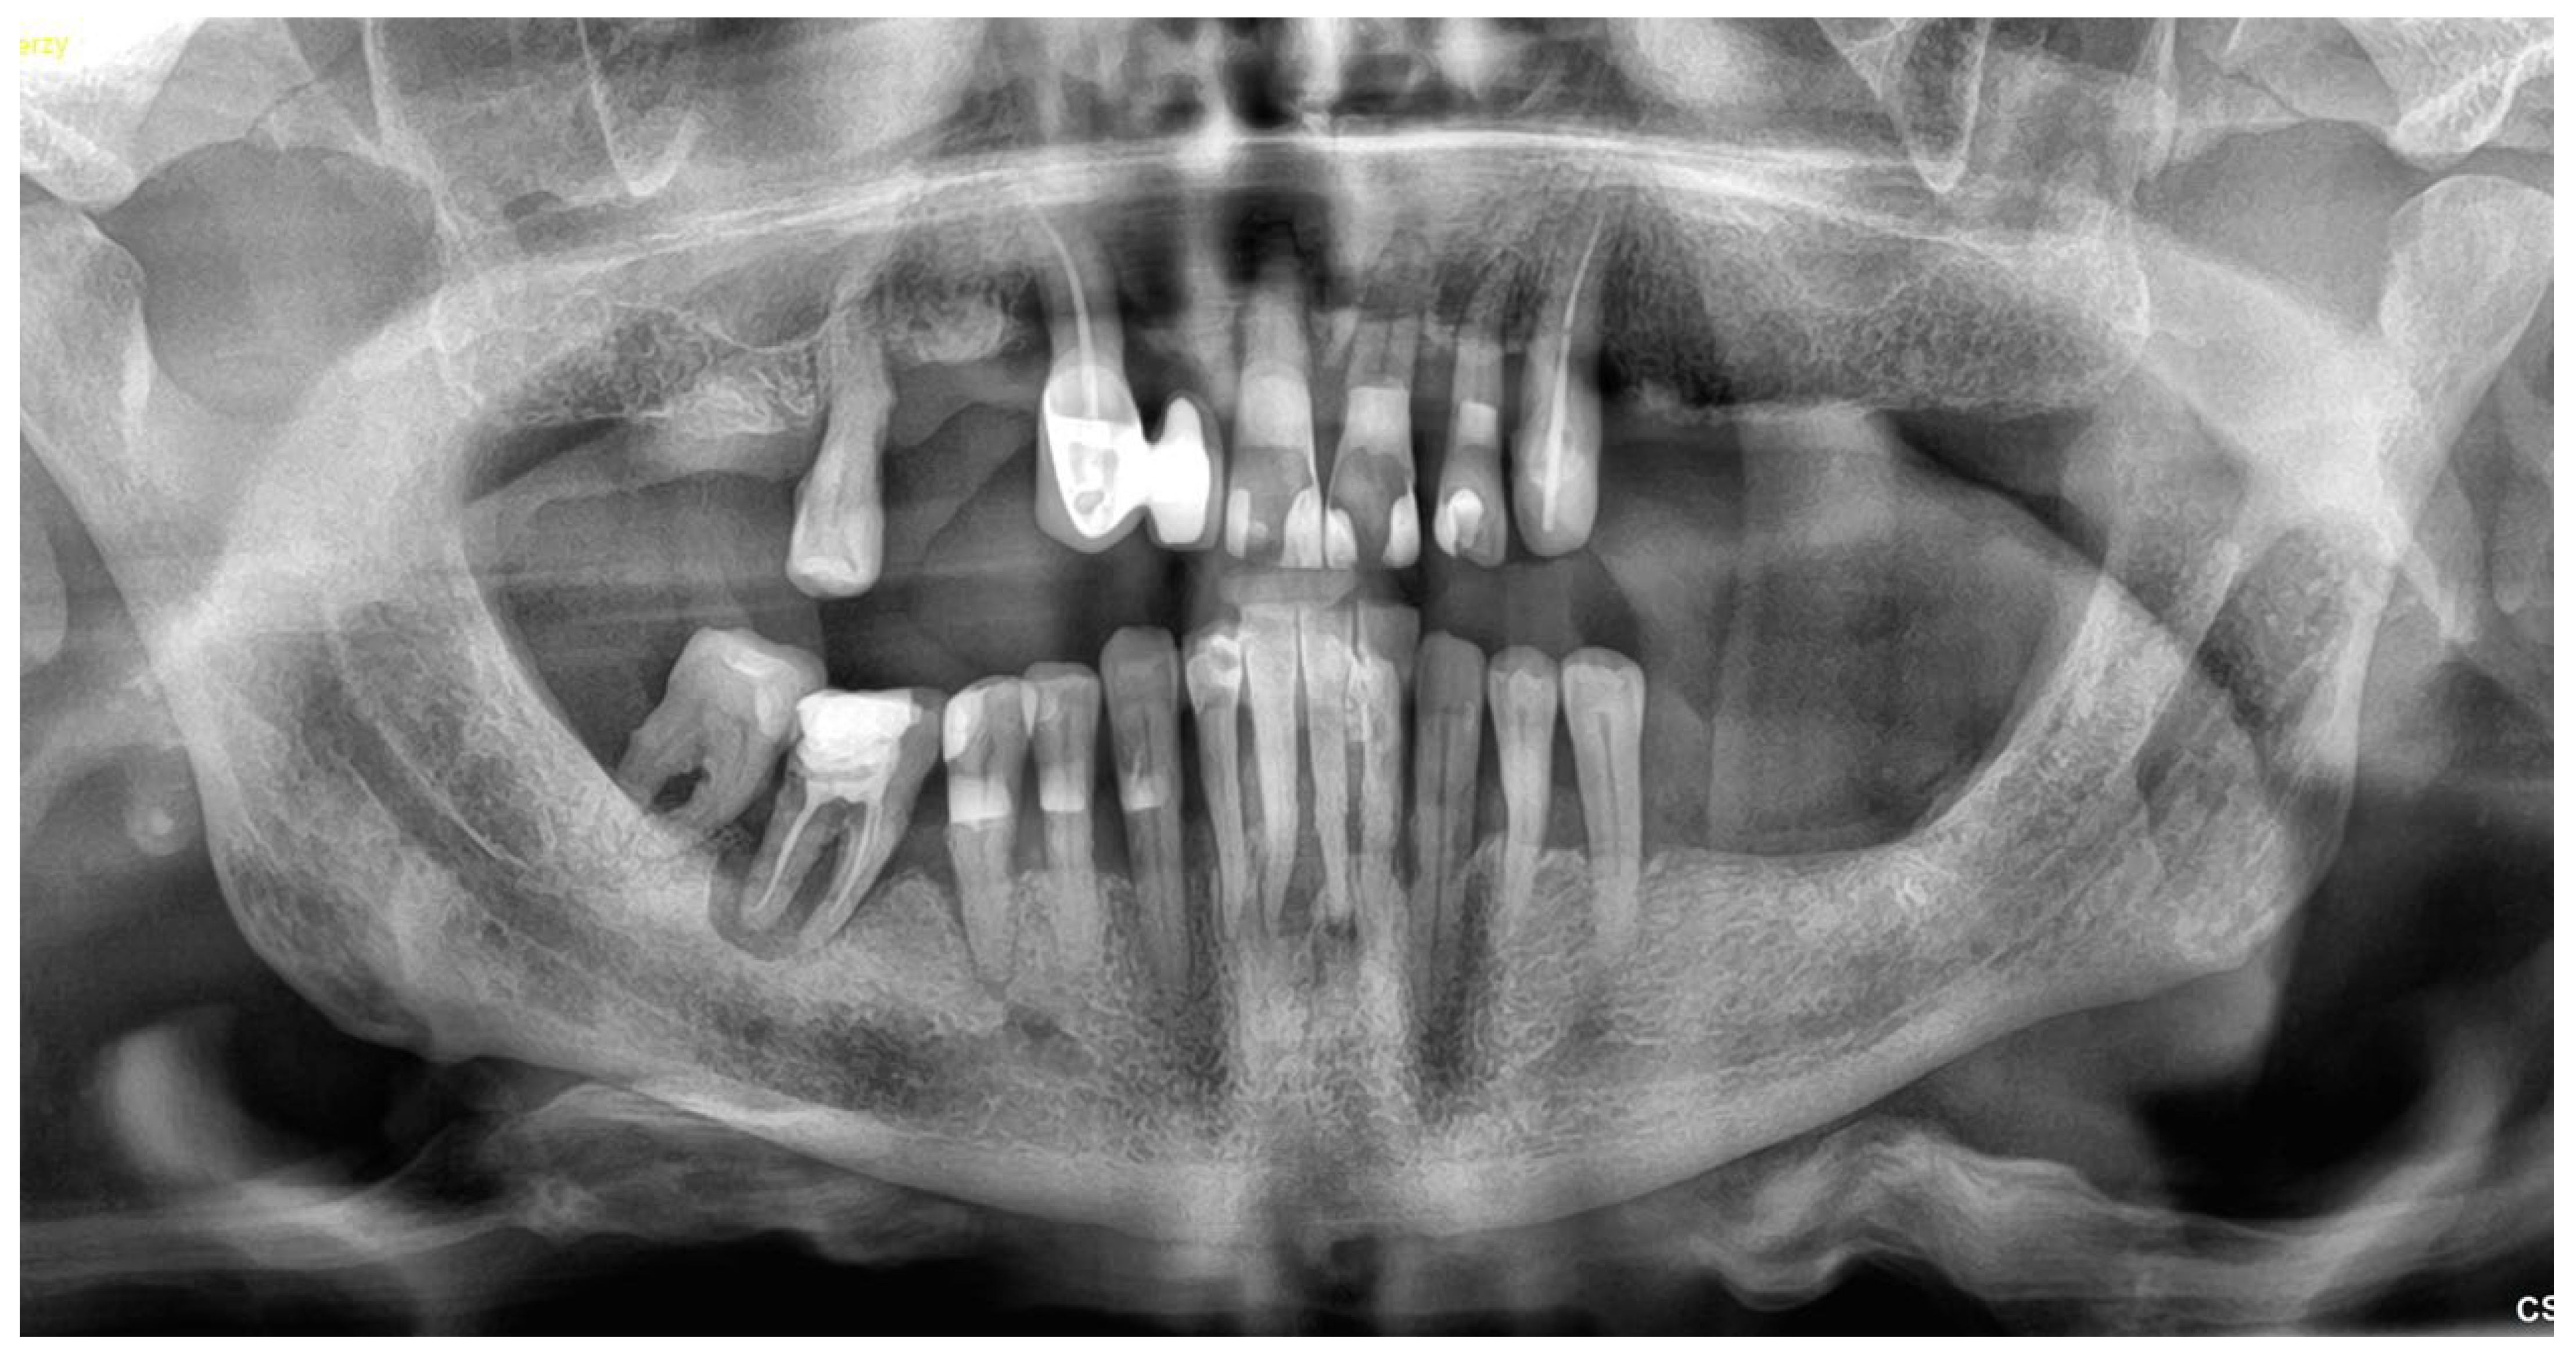

2.1. Patient Information and Clinical Findings